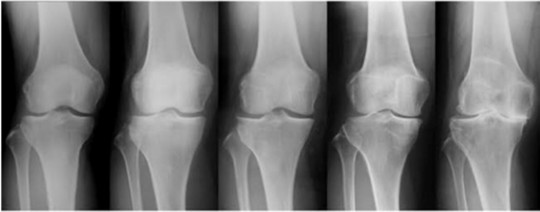

膝関節には、3つの動きがあります。

それは、『ころがり』『すべり』『回旋』の3つの動きになります。

膝が痛い方は特に、この『回旋』の動きがなくなる事が多くみられますが、そのほかにも『ころがり』『すべり』も制限されることは多くあります。

特に、膝の状態が悪くなればなるほど3つの関節の動きが制限されます。

TVや医療機関では『筋肉がないから痛いんだよ!』と耳にしますが、筋肉がしっかりと働くには関節が動かなければ機能しません。

関節が適切に動かない状態で筋トレしても大きな変化は出ません。

スポーツで膝を痛めた方は、ただ単に筋トレではなく、関節の機能を修正しながら筋力トレーニングが必須になります。

よって、膝の関節のうごきである『ころがり』『すべり』『回旋』のうごきを作る事がポイントになってきます。

この3つの『ころがり』『すべり』『回旋』の動きを作れば膝の機能は修正されますが、この機能を修正せずに筋トレをするといつまでも膝は痛いままになります。